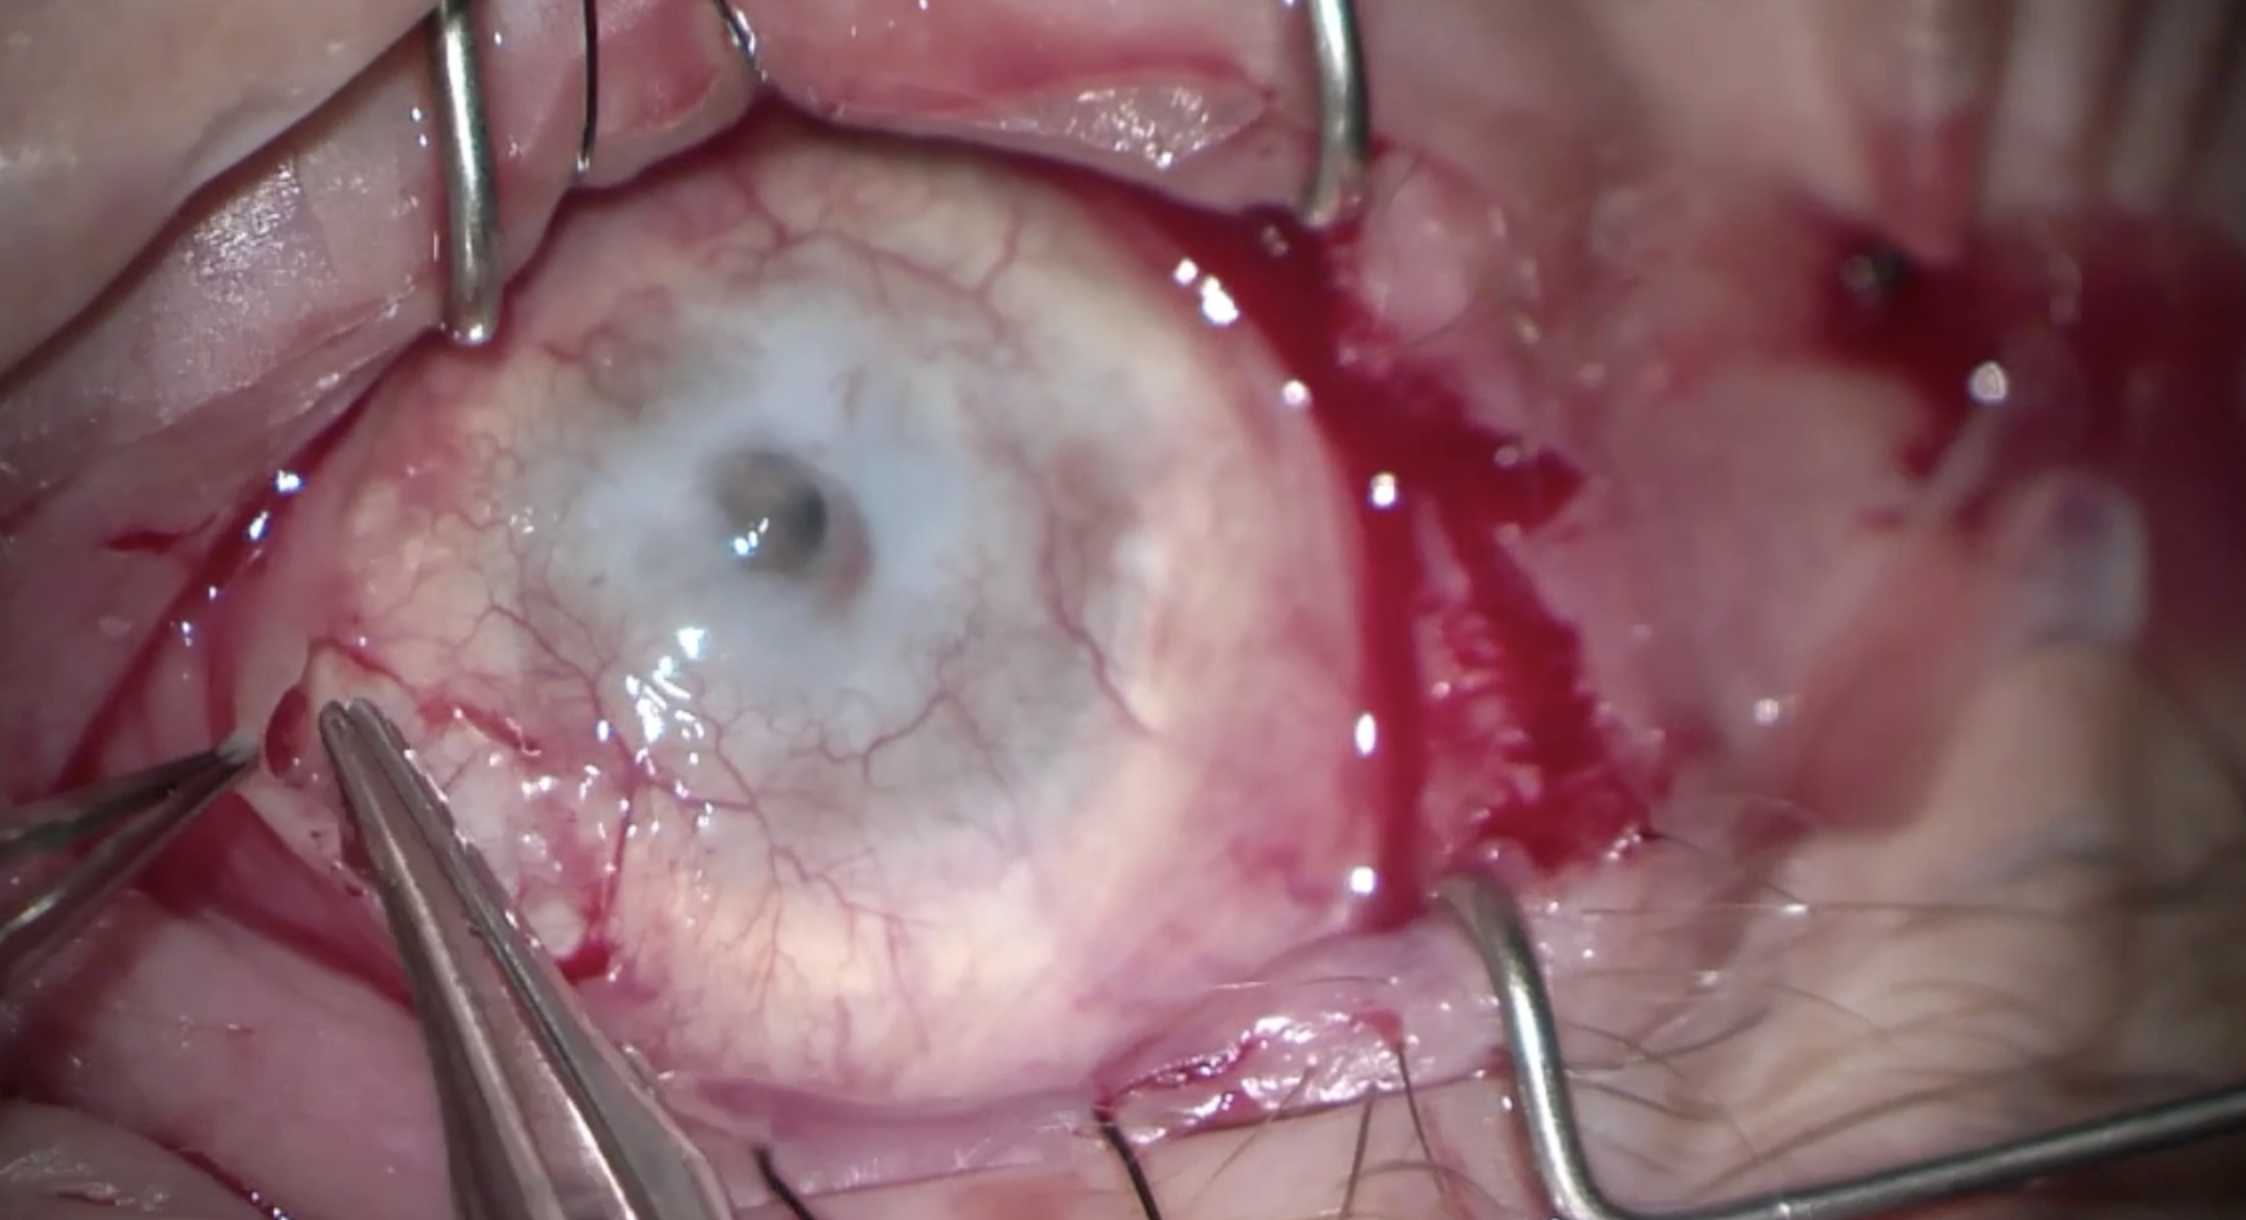

Diabetes Managed with Anterior Chamber Islet Cell Transplant A patient with past medical history of uncontrolled diabetes and open globe injury of the right eye presents with blurred vision in her left eye. She had LP vision in her right eye. Her examination demonstrated changes consistent with pri…